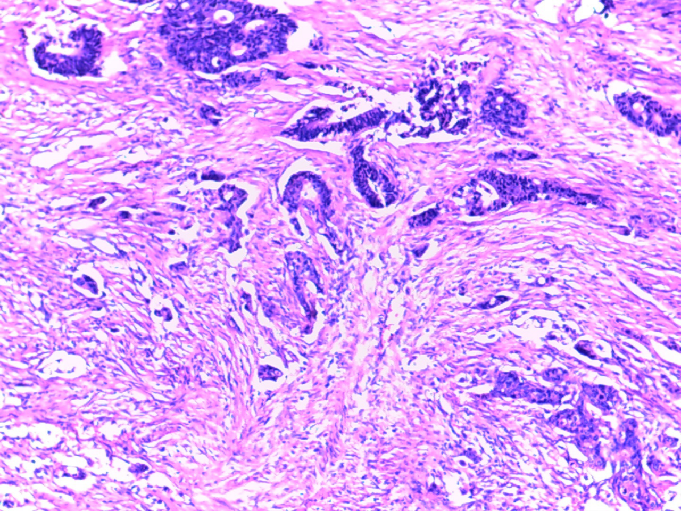

2020-02-13 术后病理

(降结肠切除标本):腺癌,中分化,溃疡型,癌组织浸润至浆膜层,见脉管内癌栓,神经见癌组织侵犯,标本上、下切缘未见癌组织残留。隆起:管状腺瘤伴低度上皮内瘤变。肠系膜查见淋巴结6枚未见癌组织转移,癌结节6枚。另见肠管壁:肠粘膜慢性炎伴局灶浅表溃疡形成,粘膜下层血管扩张、充血。

[IHC:2020069]PCK(+);Ki-67约30%+;P53(-);CDX-2(+);EGFR(±);VEGF(-);MLH1(+);MSH2(弱+);MSH6(+);PMS2(弱+)。